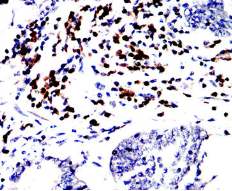

CD79A Mouse Monoclonal antibody[2E6A7]

AC1815 CD79A Mouse Monoclonal antibody[2E6A7] 100ug $367 10days

AC1815 CD79A Mouse Monoclonal antibody[2E6A7] 200ug $660.6 10days

Immunogen:    Purified recombinant fragment of human CD79A (AA: extra 33-143) expressed in E. Coli.

IHC    1/200 - 1/1000